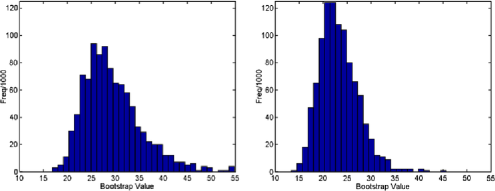

Figure 8 shows four typical examples of bootstrap distributions with and without changes detected. While differences due to the different underlying correlation structures are clearly visible, no difference is apparent between scans which contain a detected change and those which do not. Figure 9 shows the distribution of the 5% bootstrap critical values from 197 scans, once more indicating that the critical values show some deviation between scans due to different underlying correlation structures, hence different limit distributions, but do not differ between those with or without changes detected.